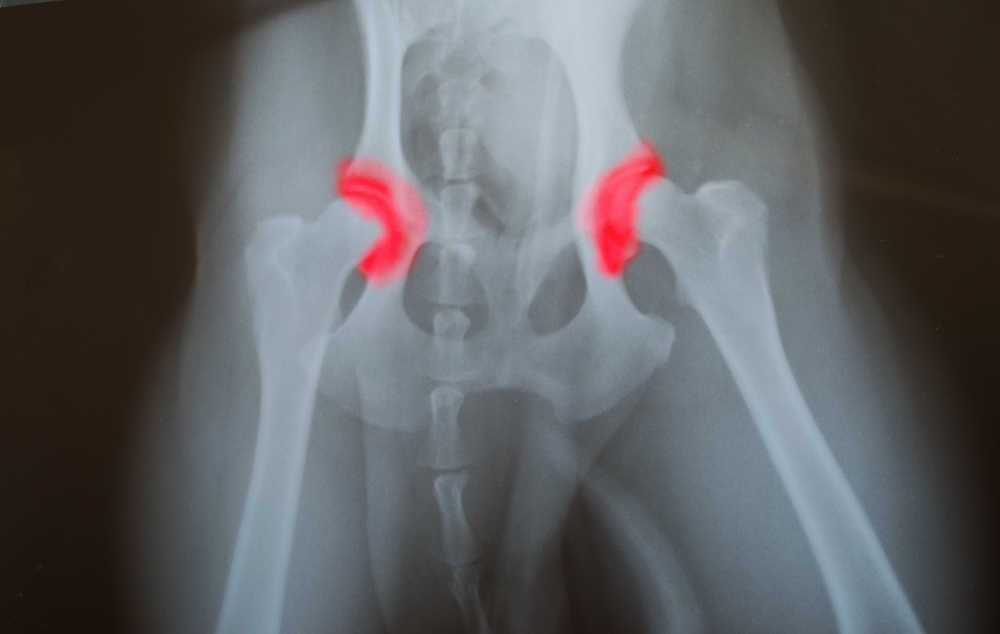

Дисплазией тазобедренного сустава (ДТС), или врожденным подвывихом тазобедренного сустава называют недоразвитие (или неправильное развитие) самого сустава или его компонентов: вертлужной впадины тазовой кости, хряща, связок и мышц, удерживающих бедренную кость в правильном положении.

При недоразвитии сустава нарушается или отсутствует правильный контакт между головкой бедренной кости и выемкой для нее (вертлужной впадиной в тазовой кости). Проявления такой патологии иногда трудно выявить родителям в раннем возрасте ребенка. Первоначальная диагностика этой врожденной патологии проводится непосредственно после рождения младенца, что позволяет не допустить ее серьезных последствий, развивающихся при позднем выявлении.

При отсутствии контакта между бедренной и тазовой костями, бедренная может свободно двигаться вне сустава. Такое состояние называется дислокацией сустава, или вывихом. Различают 2 подвида дислокации: тератологическую и типичную.

- рентгенологическое обследование (после 6 месяцев, так как в более раннем возрасте костная система недоразвита, состоит из хрящей, которые трудно зафиксировать на рентгенограмме).

- уплощение или деформация вертлужной впадины тазовой кости;

- частичное (или полное) выхождение бедренной кости из вертлужной впадины.